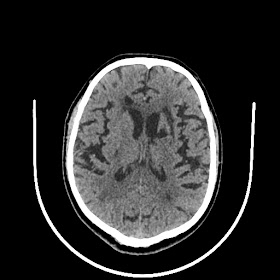

39 years old man with chronic alcoholic since 17 years.

& cough with cold & dark colour stool.

Now feeling weakness & dimness of vision.

O/E images: